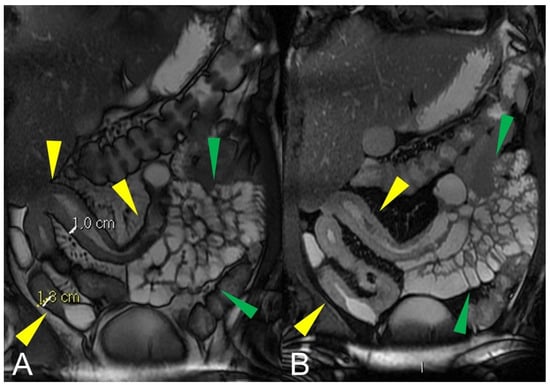

Figure 1.

Quantification of intestinal strictures. Coronal fast imaging employing steady-state acquisition (FIESTA) images (A–F) show a long segment of the distal ileum affected by pathology (yellow arrowheads) showing, reduction in caliber, stiffness, and absent peristalsis. The upstream loops are extremely dilated (green arrowheads) indicating that, although a tight stenosis of the lumen is not appreciable, the long segment reduced in caliber behaves as if it were a pre-occlusive stenosis, preventing the transit of intestinal contents with massive dilatation of the upstream loops. This condition represents a functional stenosis that needs to be treated surgically to prevent repeated subocclusions or intestinal obstruction or other complications.

Figure 2.

Quantification of intestinal strictures. Coronal fast imaging employing steady-state acquisition (FIESTA) images (A,B) show a long segment of the distal ileum affected by pathology (yellow arrowheads). The upstream loops do not show dilatation (green arrowheads) because the pathological loops do not show significant abnormal stiffness or massive luminal reduction. This condition represents a no-functional “stenosis” because the intestinal flow is preserved, so there is no risk of sub-occlusions or intestinal obstruction.